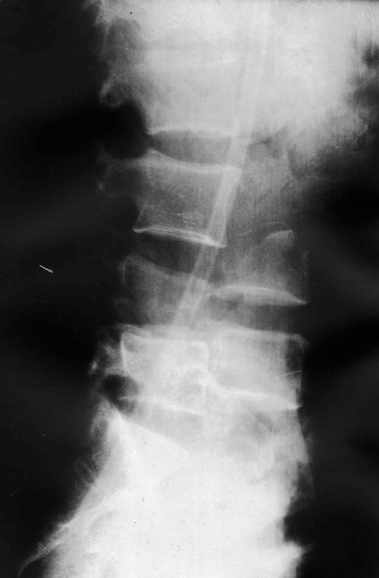

1

2

Высылаю рентгенограммы. Спасибо за рекомендации. Наша тактика согласуется с вашими рекомендациями за исключением транспедикулярной фиксации - у данного пациента на наш взгляд предпочтительнее наружная транспедикулярная фиксация (Курганский аппарат). Погружная конструкция предпологает одномоментную репозицию до выполнения забрюшинного доступа и ревизии переломов что теоретически может привести к повреждению дурального мешка и корешков. АВФ позволит восстановить ось позвоночника и смещение по длине непосредственно под контролем глаза на этапе внебрюшинного доступа. Сколько сегментов замыкать? Я думаю может потребоваться замкнуть и сегмент L2-L3. Предполагается использовать тело L4 для костной пластики таким образом, чтобы ширина спиномозгового канала на уровне оперированных сегментов была увеличена. Фиксация тел позвонков вентральной пластиной.